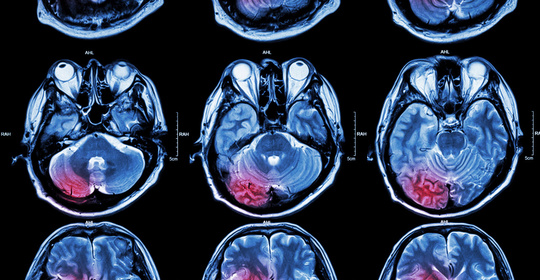

大腦大靜脈畸形:症狀、病因、看醫生、檢查、治療

大腦性共濟失調:症狀、病因、就診、檢查、治療

大腦鐮旁腦脊膜瘤:症狀、病因、看醫生標準、檢查方法、治療方法

大腦麻木:症狀、病因、就診、檢查、治療

大腦大靜脈擴張:症狀、病因、治療、檢查、看醫生